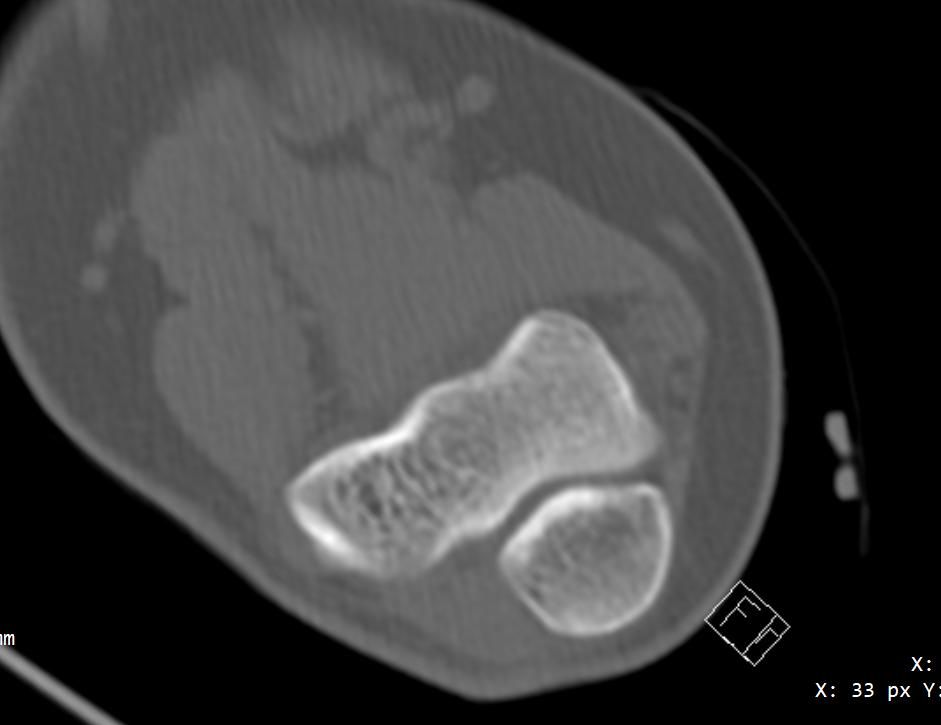

10년전 왼팔의 두 뼈가 골절됨과 동시에 휘어져서 응급실에서 뼈를 돌려서 맞추고 깁스를 했는데 그 이후로 왼쪽으로 팔이 회전하지 않습니다 ct 사진도 첨부해드리겠습니다

사진상 "요.척골이 회전 변형된 채로 붙은 부정유합" 가능성이 커 보입니다.

이 경우 팔꿈치.전완 "회전 제한(회내/회외 장애)"이 오래 지속될 수 있습니다.

올려주신 사진과 증상을 참고했을 때, 팔꿈치 관절을 구성하는 요골과 척골의 정렬이 크게 뒤틀려져 보이지는 않지만 골절 유합시 미세한 각 변형이나 척골과 요골 사이 인대와 같은 연부조직의 유착 또는 요골과 척골의 관절의 기능이상등으로 인해 나타나는 증상으로 생각됩니다.